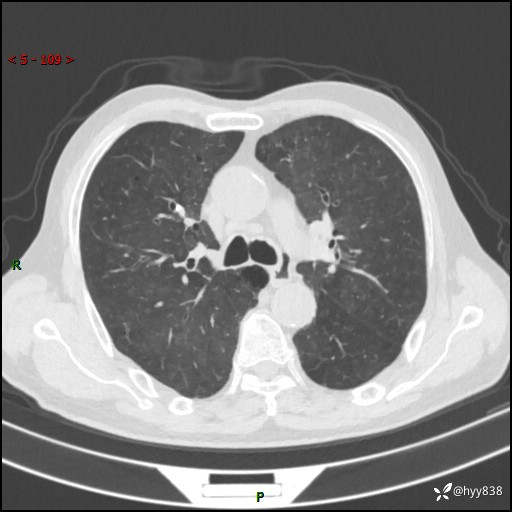

辅助检查:CT

胸部CT平扫